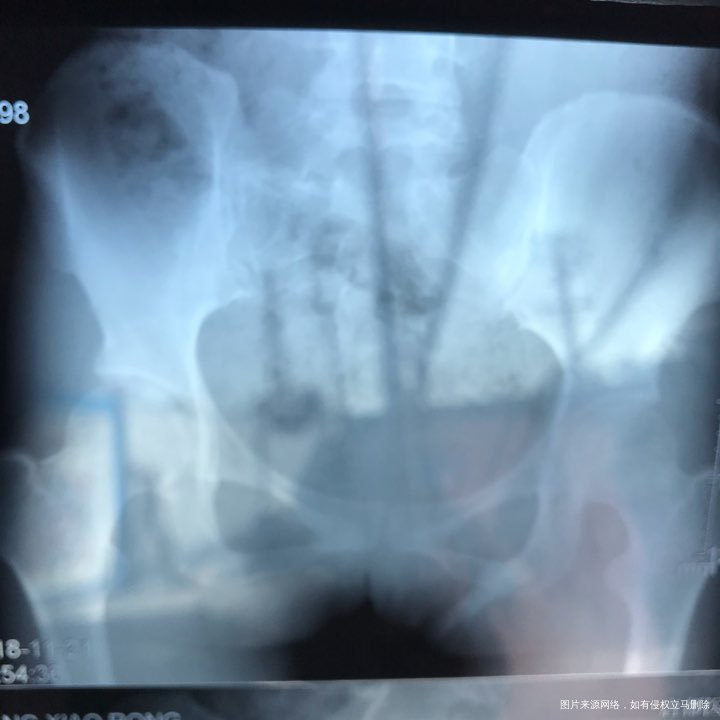

备孕时常1年,前期的检查都做了正常,帮忙看下我的输卵管造影片子吧??

您好,看着像是伞端堵塞了。

您好,考虑输卵管堵塞。建议遵医嘱。

您好,输卵管堵塞,建议切除输卵管做试管,保守保守治疗没有多大意义,觉着我的回复对您有帮助记着帮忙点击采纳,谢谢!